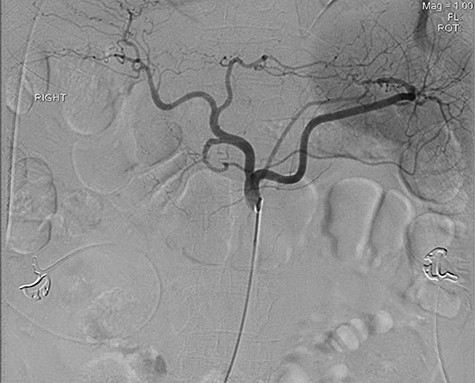

A 56-year-old African American male presented in 2015 with abdominal pain, with associated melena and hematochezia. The patient has a history of chronic back pain for which he takes 600 mg ibuprofen daily, alcohol abuse, tobacco use and a previous GI bleed in 2011, which necessitated 6 units (U) of packed red blood cells (PRBCs) and emergency therapeutic endoscopy. The patient was found to be hypotensive to 76/56 mm Hg, and hemoglobin (Hgb) was found to be 9.4 g/dl, from a previous baseline of 10.6 g/dl. His rectal examination was guaiac positive. A repeat Hgb was found to be 6.5 g/dl. The patient was given 3 U of PRBC and an emergency endoscopy was performed. On endoscopy, the patient was found to have a 6 cm gastric ulcer with an associated vessel underneath of a large clot. Due to the high risk nature of the bleed, it was felt by the gastroenterologist that the patient should undergo an endovascular angioembolization (Fig. 1). The patient was brought to the Interventional Radiology Suite for the procedure. The patient’s right common femoral artery was accessed and the celiac trunk was selected. A subselective common hepatic arteriogram was performed, which demonstrated active extravasation arising from the proximal aspect of the GDA. The GDA was then coil embolized both proximal and distal to the site of bleeding using five microcoils. Repeat arteriogram demonstrated no further opacification of the GDA and no further extravasation (Fig. 2).

Demonstrating active extravasation of the GDA during a subselective GDA arteriogram

Demonstrating coil embolization of the GDA with no opacification